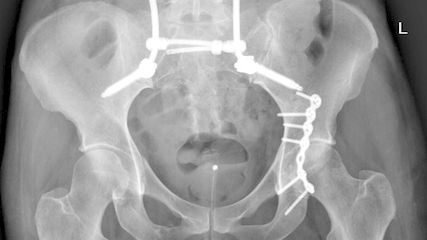

Alle Patient:innen wurden von 2 Senior-hauptoperateuren über einen posterioren Zugang operiert, aus hygienischen Gründen wurden keine vorderen Zugänge angewandt. Bei vielen Patient:innen sind Pilzerkrankungen in der Leiste zu beobachten, daher sollte der Zugang nach Meinung der Autoren einen möglichst grossen Abstand von der Leiste haben. Dies wird durch eine Publikation von Watts untermauert, der eine deutlich geringere Infektionsrate beim posterolateralen Zugang im Vergleich zum anterioren Zugang beschrieben hat.12 Alle Prothesenpfannen wurden zementfrei verankert, 6 Patient:innen erhielten eine Double-Mobility-Pfanne. Die Arbeitsgruppe von Hernigou hat bei sehr adipösen Patient:innen eine Reduktion der Luxationsrate von 21,8% auf 2,8% durch Verwendung von Double-Mobility-Pfannen erreichen können.13 12 Patient:innen wurden mit zementfreien Femurkomponenten versorgt.